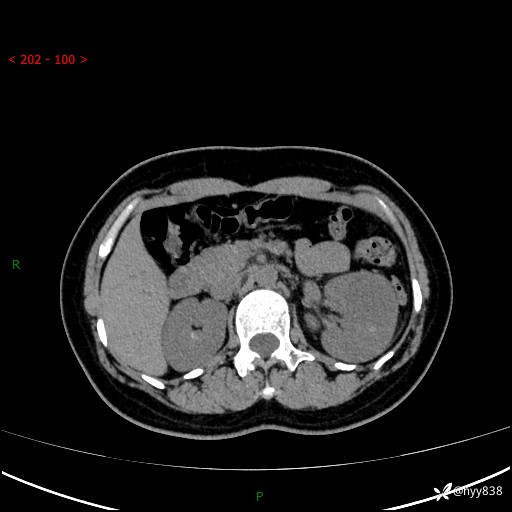

现病史:患者于1周前因左侧腰腹部间断胀痛不适,无恶心呕吐,无明显肉眼血尿,无畏寒发热,无尿频尿急,起病初,患者来我院就诊,查CT提示左肾低密度影,外周血提示:白细胞11.25*10^9/L.行抗感染治疗后未见明显好转,06-18泌尿系增强CT提示左肾类圆形低密度占位(脓肿?肿瘤?),大小:4.0*3.2cm,为求进一步治疗,门诊以“左肾占位”收住我科。 起病以来,患者精神佳,饮食、睡眠良好,大小便正常,体力体重无明显变化。

双肾CT平扫+增强